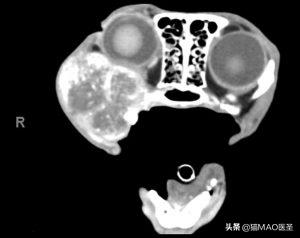

CT可以提供更多信息,因为它可以显示疾病的程度,用于治疗计划(手术或放射治疗)(图7)。建议在CT检查中包括胸部,以评估可能的肺转移性疾病。

最重要的是,如果放射治疗是一个治疗的考虑,CT扫描应该在相同的设施进行治疗,因为可能需要CT辐射规划和设置。

计算机断层扫描的猫与增殖性右上颌肿块,组织学证实为猫口腔鳞状细胞癌。